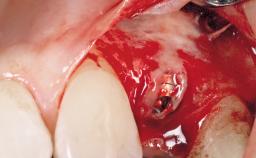

After the placement of three diameter-reduced two-piece implants the bone is augmented with autologous bone chips and DBBM particles to enlarge the crest volume. The surgery is completed with the application of two membrane layers and primary wound closure.

For soft tissue management, the initial healing caps are replaced with a longer type 8 weeks after implant placement in a second intervention before prosthodontic treatment is initiated.

The case concludes with the presentation of the final prostheses at the 3-year follow-up, demonstrating a stable and pleasing soft- and hard-tissue situation.